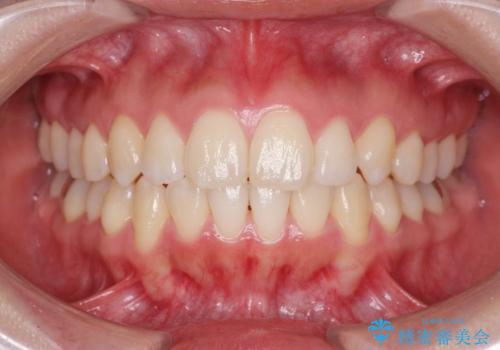

矯正治療後、前歯のがたつき、咬合関係が改善され満足いただくことができました。